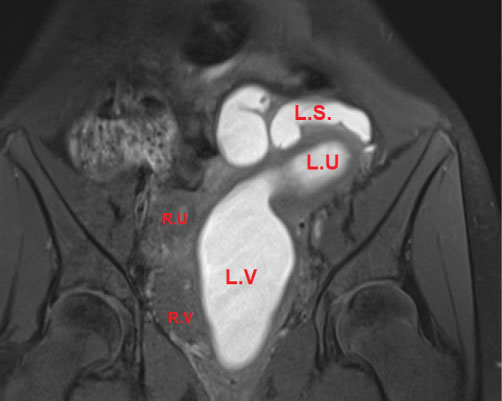

Pelvic MRI showed uterus Didelphis with two hemi-uteri and two hemi-vaginas, the left hemi-vagina was blind, (Figure 1), left hematometro-colpos, and hematosalpinx overlying the dome of the urinary bladder (Figure 2 and Figure 3), Also, it showed left renal agenesis (Figure 4).

Figure 2: MRI image coronal view.

LU: Left uterus horne, Dilated (metrocolpos) >; LV: Left vagina, Dilated (Hematocolpos); LS: Left salpinx (hematosalpinx); RU: Right uterus horne; RV: Right vagina. View Figure 2